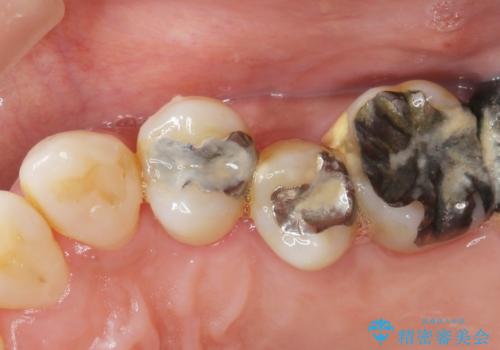

- 全体的に歯が揺れ、このままでは全て歯を失うのではないかと怖くなり歯周病治療を希望され来院されました。

歯列不正による第一小臼歯の骨吸収が認められ、機能咬合力の回復、大きな側方力に連結することで抵抗することのできるブリッジ補綴を選択しました。

歯周病による深いポケット・大きな側方力・短い臨床歯根・欠損の補綴、これらの問題を解決するために歯周補綴を兼ねたブリッジを選択しました。